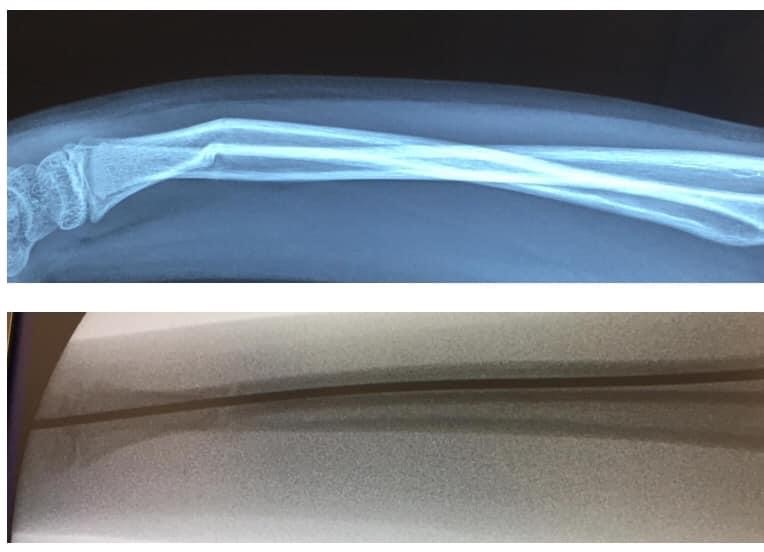

小童的骨質軟而有彈性,不用很大外力就能折彎,因此稍一不慎在耍樂蹦跳期間跌倒或從稍高位置跌下就有可能造成骨折。

常見會有外觀變形、彎曲的情況

醫生會先以X光去確定受傷位置和骨折的嚴重程度